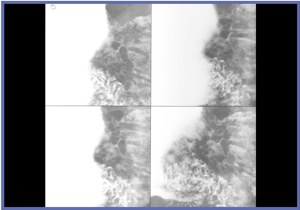

精度向上に直接つながる熟練した撮影技術の会得には,日常的にびらんを撮影することが有効である。びらんは,アレアとともに胃の凹凸の中では最小サイズであるため,これを意識的に撮影することが日々の訓練となる。がんは,日常的にはほとんど遭遇しない(発見率0.3%程度)が,びらんの所見は18%程度ある。当院のびらん所見を調べたところ,形状はたこいぼびらんが80%を占め,占拠部位は83%が前庭部に集中していた。前庭部前壁二重造影,前庭部空気少量二重造影,圧迫,後壁二重造影などでびらんを撮影することが,技術向上に有効であろう。前庭部のバリウムと空気が入れ替わる一瞬のびらん撮影(図7),ていねいに圧迫してびらんをびらんらしくとらえる(図8)など,びらん撮影はテクニックを磨く上で重要である。

![]() 図7 前庭部空気少量二重造影 |

![]() 図8 圧迫撮影 |